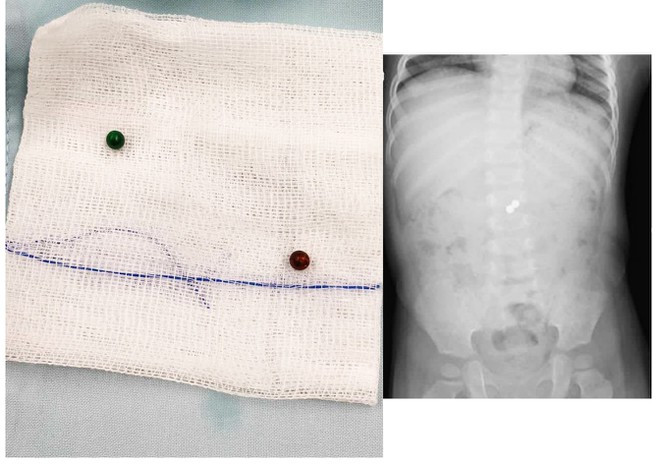

| Viên bi nam châm được lấy ra ngoài và qua hình ảnh X-quang khi ở trong ruột bệnh nhi (phải) BVCC |

Tại Bệnh viện Nhi đồng Thành phố, bệnh nhi được thăm khám và chụp chiếu phim X-quang kiểm tra. Các bác sĩ phát hiện hai dị vật cản quang tròn nhỏ nằm gói gọn trong lòng bụng, khu vực ruột non.

Sau sáu tháng trời bị nuốt vô bụng, 2 viên bi nam châm nằm ở hai khoang ruột khác nhau nhưng đã hít chặc vào nhau, làm cho hai đoạn ruột bị kéo dính lại với nhau. Dần dần thành ruột bị xuyên thủng, bị bao lại, dọa tắc và nguy cơ hoại tử ruột.